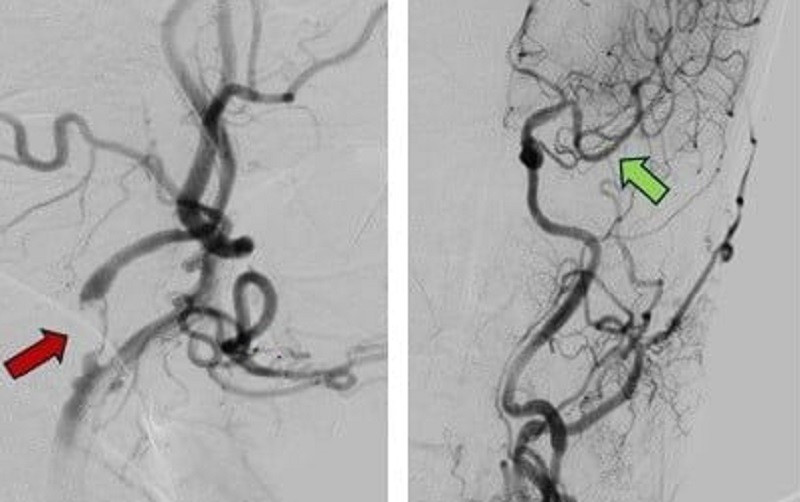

Hình ảnh mạch máu bị tắc (mũi tên đỏ) và mạch máu được khơi thông sau can thiệp (mũi tên xanh)

Chẩn đoán bệnh nhân bị tổn thương não nặng rất nặng, các bác sĩ lập tức kích hoạch chế độ báo động đỏ đột quỵ. Theo kết quả chụp CT-scan, bệnh nhân bị tắc động mạch cảnh trong và động mạch não giữa bên trái – hai nhánh chính nuôi dưỡng phần lớn bán cầu não.

Sau hội chẩn và chỉ định can thiệp, bệnh nhân được chuyển vào phòng can thiệp mạch số hóa xóa nền. Một ống thông siêu nhỏ được luồn từ động mạch đùi lên tận não để tiếp cận vị trí tắc. Sau 55 phút thao tác căng thẳng, các bác sĩ đã lấy ra cục huyết khối, dòng máu não tái thông hoàn toàn, giúp não được tái tưới máu.